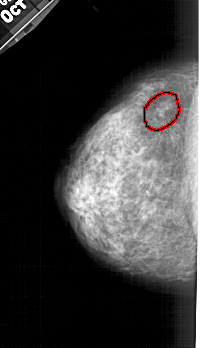

A_1427_1.RIGHT_CC

RIGHT_CC LINES 4666 PIXELS_PER_LINE 2746 BITS_PER_PIXEL 12 RESOLUTION 43.5 NON_OVERLAY

FILE: A_1427_1.LEFT_CC.OVERLAY

TOTAL_ABNORMALITIES 1

ABNORMALITY 1

LESION_TYPE CALCIFICATION TYPE AMORPHOUS DISTRIBUTION CLUSTERED

ASSESSMENT 4

SUBTLETY 3

PATHOLOGY BENIGN

TOTAL_OUTLINES 1

BOUNDARY